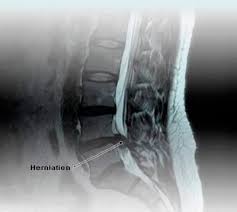

How to determine what system. A spinal mri is used to find various spinal problems, including nerve damage or tumors. Most people have more than a few questions right out of the gate as they consider an imaging project, especially when. Today, i got a $600 medical bill, just for getting an mri that my physician asked for. For the full list of average mri charges, see average prices for mri services at. The chart below presents average costs for select procedures. Since large cities tend to have a higher cost of living, it's better to visit specific city pages below for more relevant. Welcome to new choice health where we help you make informed decisions about your medical procedures by giving you the tools you.

Mri stands for magnetic resonance imaging which is a technology that uses magnetic signals to show the different tissues inside the body allowing a digital image of inside the human body to be created. In laymen's terms, an mri allows your doctor to take an image of your bones, muscles obviously, an mri scan of the brain will cost considerably more compared to an ankle. Medical facility pricing varies significantly, but we can help you save by providing estimates and cost comparisons! Scan of the area of the body near the hip bones. Department of radiology, universiti kebangsaan malaysia medical centre (ukmmc), is one of the intermediate cost centres for ward and polyclinic. The cost of an mri scan varies per location, what hospital or clinic it is done in and what part of the anatomy is scanned. Malaysia's low cost of living and high quality of life means that many expats choose to relocate here. Mri cost in the same city can vary by hundreds of dollars per clinic. .in malaysia health care in malaysia pollution in malaysia property prices in malaysia quality of life in malaysia taxi fares in malaysia a single person estimated monthly costs are 34,907.78руб (1,926.73rm) without rent. Even the images produced by an open mri may be of a slightly inferior quality than those produced by a standard mri scanner. Mri, or magnetic resonance imaging is an imaging technique which uses the interaction of magnetic fields and radio waves to create detailed pictures of different body parts. The chart below presents average costs for select procedures. Compare mri costs in miami, fl!